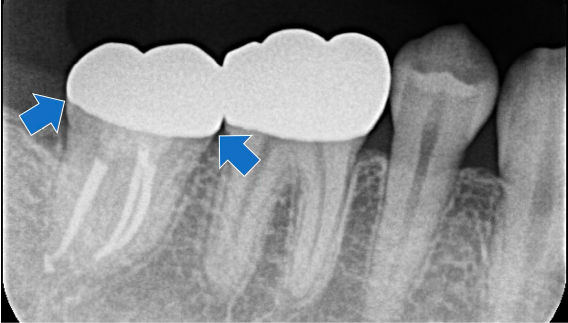

フォローアップ

術後6ヶ月時点で症状は消失していましたが、他部位の治療が必要であったため、そのまま術後12ヶ月まで経過観察となりました。

術後12ヶ月時点で全く痛みはなく、レントゲン画像でも問題なく治癒していたため、セラミッククラウンへ移行しました。

セラミッククラウン

今回根管治療を行ったのは最後方臼歯である右下7番でしたが、手前の6番にも虫歯があったため、虫歯の再発リスクを極力減らす目的でセラミッククラウンによる補綴治療を行いました。

装着後のレントゲン写真

根管治療を行った歯の予後に大きく影響するのが、補綴治療の質、つまりピッタリと歯に適合した隙間の少ないクラウンが装着できるかどうかです。せっかく根管治療がうまく治っても、クラウンの精度が低いと、将来的に虫歯の再発(二次う蝕)のリスクとなり、根の問題の再発や歯の再治療が必要となる可能性があります。今回のように、根管治療に加えて適合のよい修復物を入れることも、歯の健康のためにも重要といえます。